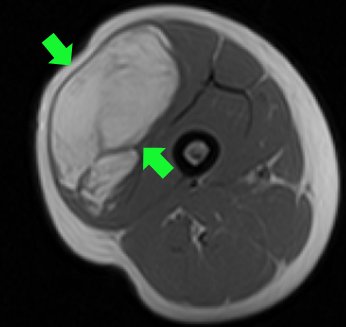

Yumuşak doku tümörleri de kemik tümörlerinde olduğu gibi iyi huylu yada kötü huylu olabilir. Kötü huylu olanları gene kemik tümörlerinde olduğu gibi “sarkom” olarak adlandırılır. Ancak bu, yumuşak doku sarkomudur. Yumuşak doku sarkomlarının tedavisi çoğu zaman cerrahidir ve geniş rezeksiyon gerektirir. Ameliyatta geniş rezeksiyon yapılarak tümör, etrafında sağlam doku ile birlikte geniş olarak çıkartılır (resim-18).

Bazen bir sarkom, damar yada sinir yapılarına çok yakın olabilir. Hatta bazen bu gibi önemli yapılar tümörün içinden geçebilir. Bu durumda bu yapılar kesilerek feda edilir ve tümörle beraber çıkarılır. Bu hastalara aynı seansda damar yada sinir nakli yapmak da gerekecektir. Bu operasyon sırasında geride tümörlü doku kalırsa nüks kaçınılmaz olur. Bunun cerrahisi ise daha da zor olacaktır.